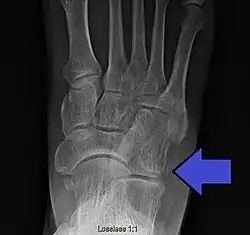

Avulsion fracture of the right cuboid bone of the foot

A cuboid fracture is a fracture of the cuboid bone of the foot. Diagnosis is by X-ray imaging, magnetic resonance imaging, or bone scan.[1] Treatment may be conservative or involve surgery, depending on the type of fracture.[1] They are rare.[1]